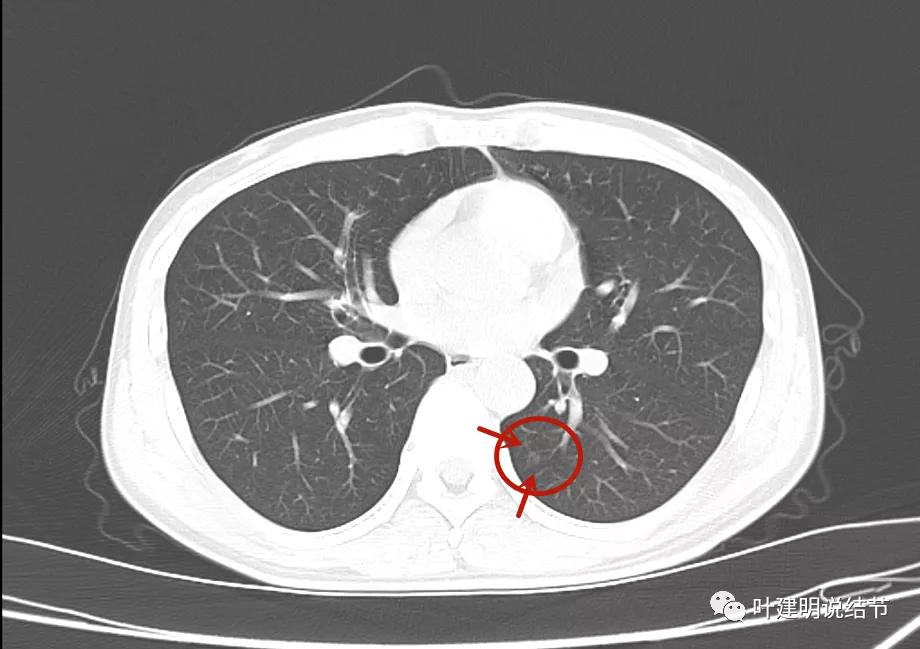

但可惜当时不是薄层扫描的。后来口服莫西沙星6天,并于2021年11月复查的是薄层的:

病灶1几乎没什么变化,实性部分范围感觉略大,显模糊。我考虑是因为薄层的关系,不是病灶有明显变化,轮廓仍是不清的

病灶2仍是极淡的,但也没有消失,有微血管贴边走行,间隙不清,此灶倒是要考虑不典型增生之类的范畴的病灶,虽然小又淡。

病灶3较前感觉明显了点,但我仍考虑也是扫描条件不同的关系,不能认为是进展。